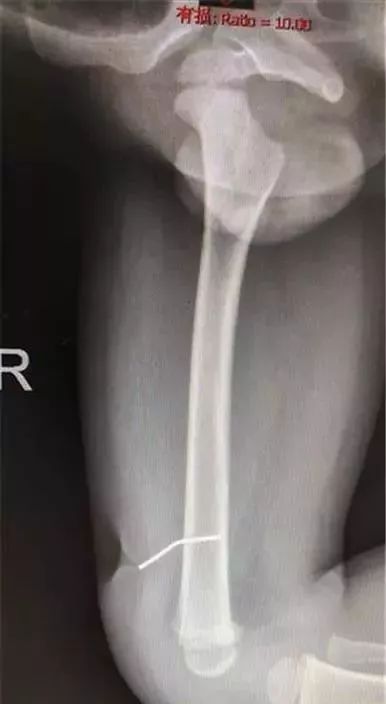

拍片显示,射钉已经深入孩子大腿股骨

医生沿着孩子大腿上凹陷伤口处探入

切开皮肤和皮下组织后

探查到一个直径约为1毫米

铁钉样的金属异物,尾端已经深入股骨

专家将异物顺利拔出, 钉子长约3厘米